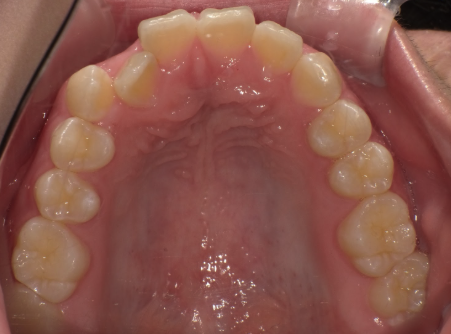

クロスバイト

治療前

ガタガタを主訴に当院を受診され、右上2番にクロスバイトを認めました。IPRを使用してマウスピース型矯正装置(インビザライン)を使用し改善を行いました。